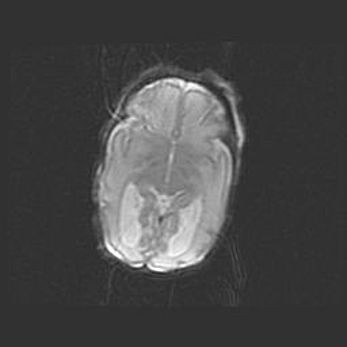

Неполная лизэнцефалия (пахигирия). Открытая гидроцефалия.

Возраст: 17 дней

Вес: 3110 г

Пол: мужской

Окружность головы: 33,5 см

Срок гестации: 35-36 недель

Лизэнцефалия—недоразвитие корковой пластинки и мозговых извилин в результате нарушения миграции нейронов коры. Поверхность мозговых полушарий гладкая. Микроскопически выявляется отсутствие нормальных слоев коры и скопление групп нейронов в подкорковом белом веществе.

Пахигирия—уменьшение числа вторичных извилин. В пораженном полушарии нервные клетки образуют толстый недифференцированный слой с неправильно расположенными нервными волокнами и группами гетеротопных клеток. Нервные клетки незрелые. Белое вещество истончено. При этом нередко аномально развит корково-спинномозговой путь.